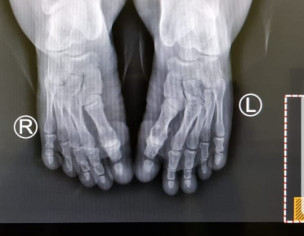

There are some deformities in the bones as seen in the xrays, would want to know about it

Developmental dysplasia of hip bilateral. (DDH). Google it u will know all about it.

there us generalised deformity of all bones and looks shortening as well and Development dysplasia of hip . looks achondroplasic

this is achondroplasia variant of AMC.